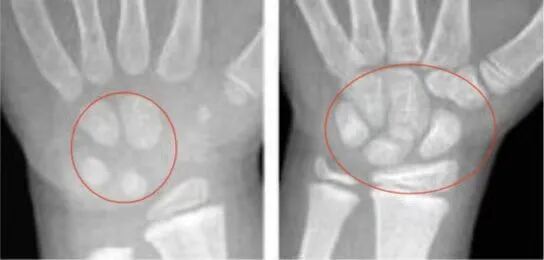

預(yù)測(cè)骨齡,專(zhuān)家建議選擇單腕關(guān)節(jié)正位片,由相關(guān)經(jīng)驗(yàn)的醫(yī)生來(lái)作出判斷。一般依據(jù)左手的X線結(jié)果:

1.依據(jù)骨間距。間距越大,生長(zhǎng)的空間越大,骨齡越小。

(骨齡小時(shí),骨間距相對(duì)較大)

2.依據(jù)腕骨的多少、密度來(lái)判斷。腕骨越少,生長(zhǎng)空間越大,骨齡越小。

(骨齡越小,腕骨數(shù)量、密度越?。?/span>